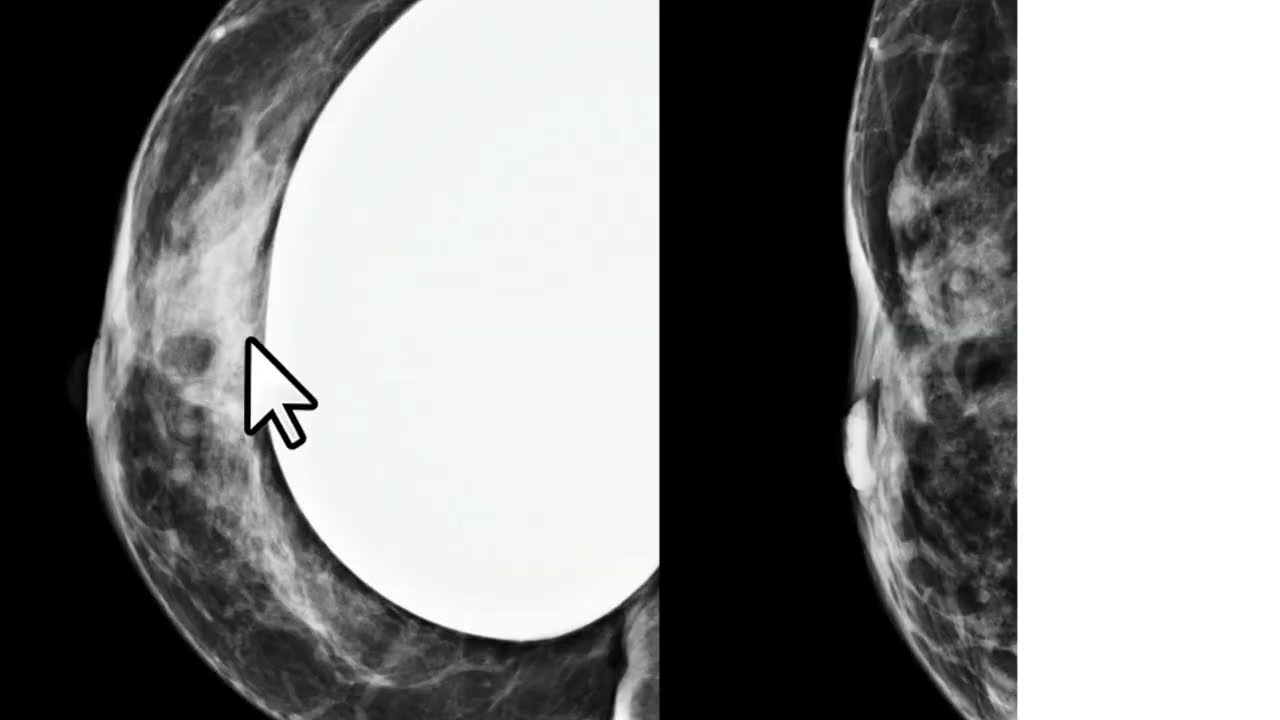

lateral-bico à direita irregular e permanência talvez especulado que seria um nódulo suspeito desde que aparecesse na incidência crê no caudal veja então que na outra incidência de rastreamento não há nenhuma imagem semelhante aquele nódulo essa situação em que a morfologia de um nó identificada em apenas uma das duas incidências de rastreamento é definida como assimetria na maioria das vezes a comparação com os exames anteriores é suficiente para segurar a benignidade do achado essa aqui é incidência médio lateral glico anterior da paciente realizado cerca de um ano antes dessa mamografia que eu mostrei para vocês veja

que nesses tema anterior a paciente tinha mais parei com a fibrilandular nos quadrantes superiores mas essa simetria que nos chamam atenção aqui na extremidade superior do Paraíso glandular não estava presente dessa forma precisamos realizar uma incidência monográfica complementar para nos certificar que esse achado e não tem importância Clínica a recomendação nesses casos é a compressão focal preferencialmente realizada na incidência em perfil veja que no perfil aparece menos um músculo peitoral maior do que aparece na incidência né de lateral oblíqua a compressão no perfil ajuda de associar a disposição do parenque os nódulos reais se Mantena